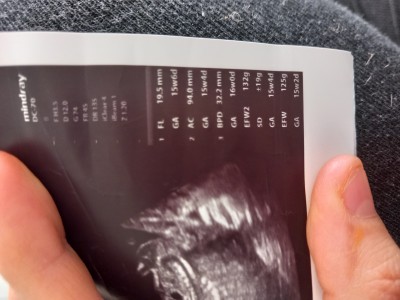

Kızlar gebelikte 11 haftalık sizce kilosu fazla degilmi

Gebelik haftası 11

Cnm k senin değildir bende pek anlamam ultrason kağıdında yazar o nün kilo değil gram da cnm bir pirinç tanesi

O senin değil bak orda 30 hafta 2 gün yazyo ona göre kilo da normal o senin değil canım baksana  30 w 2 haftaligi simgeler

Cnm altindakine bakar mısın 10.6 günlük olan ne

Onu sonradan gördüm vallahi bende çözemedim on hafta nerde otuz hafta nerde